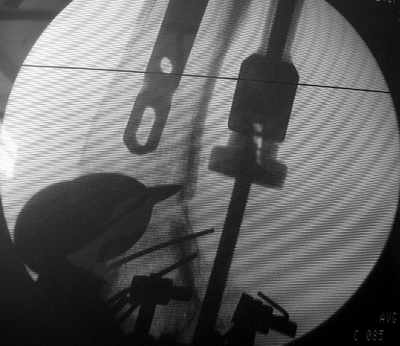

1

TAC> idea to osteotomize the femur shaft to compensate for the prior shaft malunion

TAC> was clever and should work fine.

The "idea" was an emergency appeared when the nail tip proceeded to the fracture level and became targeting anteriorly to the distal fragment.

TAC> I can't actually see the osteotomy on either radiograph. Is it more proximal

TAC> than we see in these radiographs or so well aligned as to be not visible?

The osteotomy was perfromed trough the fracture site. See the image.